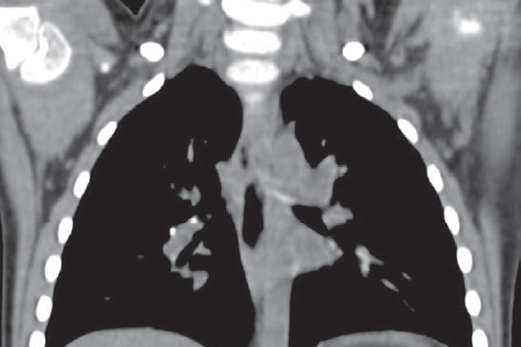

Клинический пример 2. Мальчик Л., 2 года, не привит БЦЖ в роддоме в связи с недоношенностью, затем в поликлинике не наблюдался. Кожные пробы впервые поставлены при обследовании в противотуберкулезном диспансере по контакту: реакция на ПМ и ДСТ умеренная (папула — 12 и 8 мм соответственно). При поступлении в стационар также имел картину ринофарингита, бронхита, умеренные симптомы интоксикации и периодический субфебрилитет, лейкоцитоз (12,5 ∙ 109/л). На рентгенограмме грудной клетки — инфильтрация в аксиллярном субсегменте правого легкого, корень расширен, усилен легочный рисунок. После курса антибактериальной терапии инфильтрация и корень правого легкого — без динамики, что свидетельствовало в пользу специфического поражения. КТ позволила уточнить и дополнить данные обзорного снимка: картина полного первичного туберкулезного комплекса верхней доли правого легкого с частичным обызвествлением, кальцинаты внутригрудных лимфоузлов, легочной ткани (рис. 6). Окончательный диагноз: «Первичный туберкулезный комплекс верхней доли правого легкого в фазе неполной кальцинации, осложненный очагами отсева в С2, 6, 9 правого легкого, ПЦР ДНК МБТ(+)». Такое различие в формах туберкулеза при равных социально-эпидемиологических условиях детей объясняется прежде всего наличием или отсутствием вакцинации БЦЖ, а также возрастом и преморбидным фоном.

Рис. 6. Компьютерная томография грудной клетки мальчика Л., два года (первичный туберкулезный комплекс)

Fig. 6. Chest computed tomography scan of the 2-years old boy (Ghon's complex)